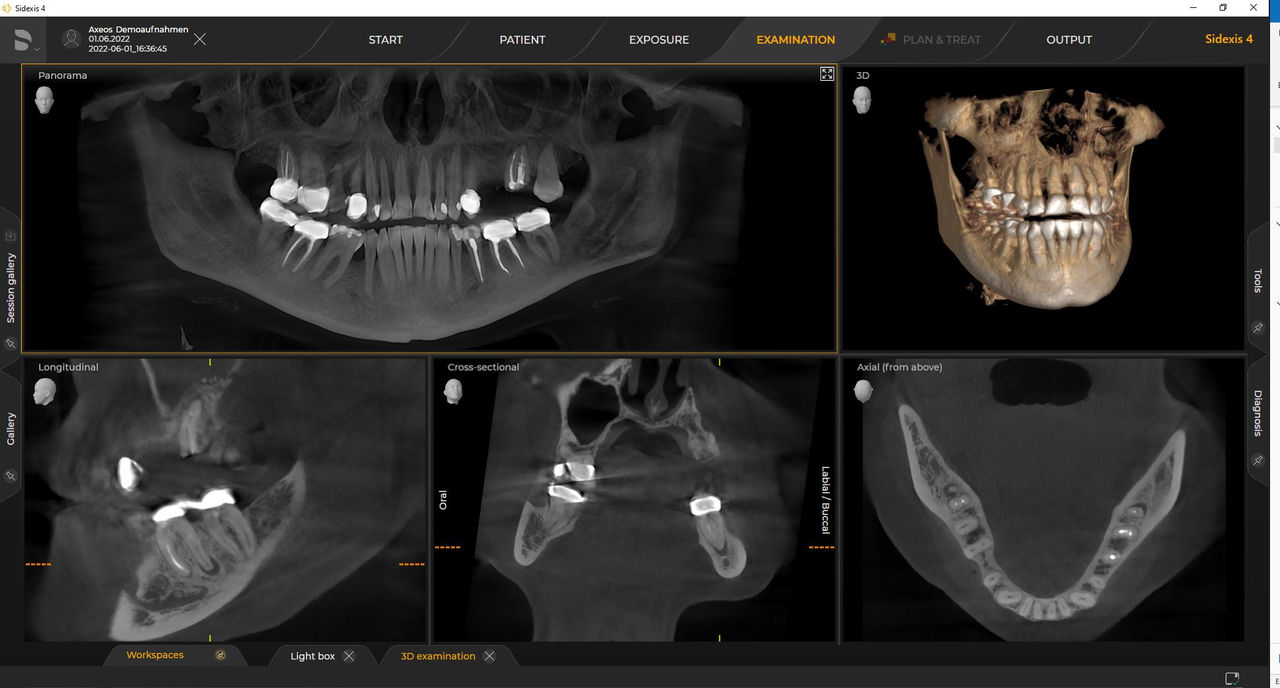

Das 2D-/3D-System mit großem Volumen und hoher Bildqualität für Praxen mit breitem Behandlungsspektrum. Gemeinsam mit Zahnärzten und Behandlern entwickelt, bietet Axeos von allen Dentsply Sirona Extraoral-Röntgengeräten das breiteste Behandlungsspektrum. Neben einer exzellenten Bildqualität und maßgeschneiderten 3D-Volumengrößen zeichnet sich das Röntgengerät durch einen hohen Patientenkomfort aus. Axeos bietet nicht nur Qualität bei Leistung und Komfort, sondern überzeugt auch durch sein preisgekröntes Design mit einem integrierten Aufbiss-Ordnungssystem und Ambient Light

Zahlreiche Volumengrößen sorgen für Flexibilität im Praxisalltag. Untersuchung eines bestimmten Bereichs oder Beurteilung der gesamten Bezahnung einschließlich der Kiefergelenke.

Dank des optimierten Low Dose Modus mit dediziertem Filter wird die Abbildung dichter Strukturen wie etwa Knochen bei stark reduzierter Dosis ermöglicht. Das macht Intelligent Low Dose zu einer attraktiven und effizienten Option bei vielen klinischen Fällen. Ob in der Kieferorthopädie oder Implantologie – mit den Dentsply Sirona Lösungen finden Sie für jeden Fall die optimale Einstellung.